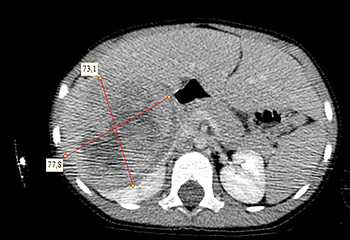

Ребенку проведена предоперационная химиотерапия. На 5-й неделе лечения КТ-контроль показал уменьшение опухоли в размерах до 90ґ80ґ100 мм (см. рис. 3).

Выполнена операция: лапаротомия, удаление опухоли правой почки с ее резекцией. Гистологическое заключение: классическая нефробластома, промежуточная группа риска (см. рис. 4).

Послеоперационная программа включала еженедельное введение трех препаратов: винкристин, дактиномицин, доксорубицин на протяжении 27 недель. Девочка перенесла лечение удовлетворительно, без осложнений, находится в ремиссии более 5 лет.